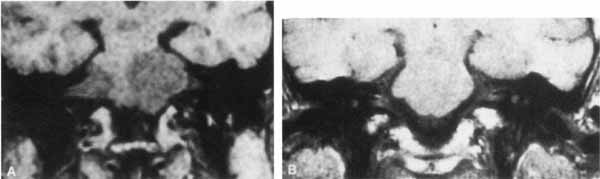

FACIAL NEUROMA

The facial paralysis associated with facial nerve neuromas usually has a gradual onset, but it may be more rapid, simulating idiopathic facial paralysis. Indeed, the pareses may fluctuate or may be associated with hemifacial spasm. In some cases, hearing loss precedes the onset of facial weakness, thereby simulating an acoustic neuroma.93 CT scan typically shows a uniformly enhancing mass in the fallopian canal. T2-weighted MRI images may show a hyperintense mass in the facial canal89 that enhances with gadolinium on T1-weighted images (Fig. 16). The ultimate diagnosis of facial neuroma requires surgical exploration and biopsy. Biopsy usually results in facial paralysis. This possibility should be discussed with the patient before surgery. Facial function recovery after resection of tumor and grafting, although never normal, may include restored tone, symmetry, and weak voluntary movement. The more facial function present before surgery, the better the results with grafting. This observation must be shared with the patient, because he or she might elect to wait until facial function is lost before consenting to surgical removal. When the tumor is located eccentrically, removal is possible with preservation of facial function.94

Fig. 16 Patient with facial neuroma. A. Coronal CT scan demonstrating enlarged stylomastoid foramen and facial nerve mass (arrow). B. Note size of canal in Figure A (black arrow) compared with normal sized canal (open arrow). C. Axial MRI scan showing an enhancing mass of tympanic segment (arrow). D. Coronal gadolinium-enhanced MRI section demonstrating same mass in mastoid segment (arrow).